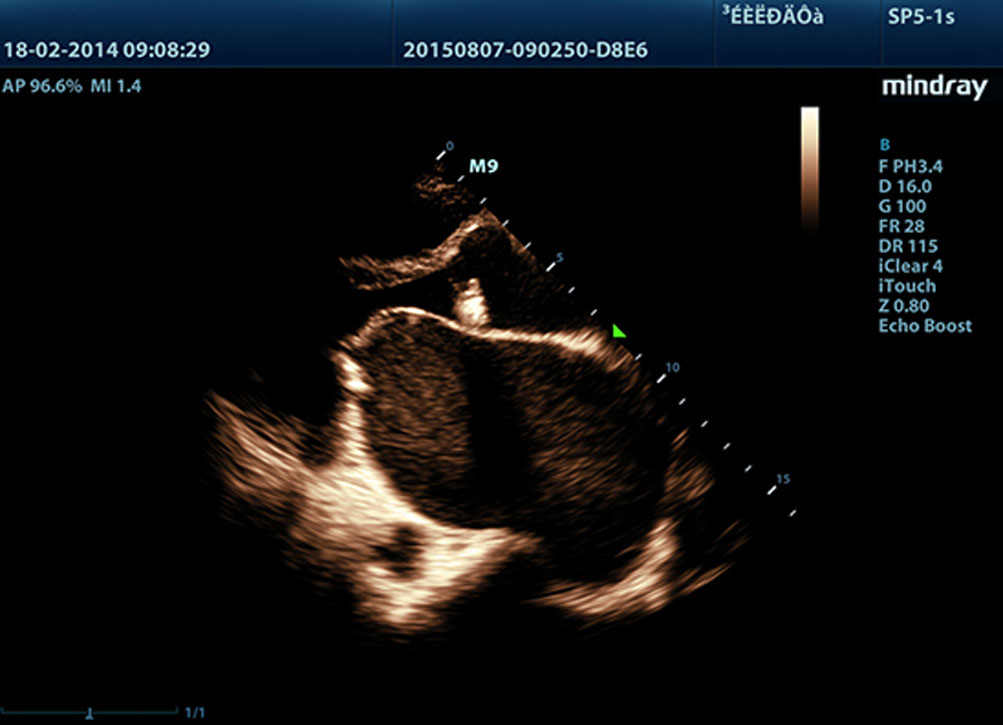

LVO with Stress Echocardiography

M9ŌĆÖs premium capabilities allow for LV opacification during stress, enhancing discrimination between myocardial tissue and blood pool, providing better visualization of the endocardial surface. Stress Echo feature on M9 includes a complete package for pharmacological stress and exercise stress echo. The package is supported by a flexible reporting system that can be optimized for your individualistic needs.